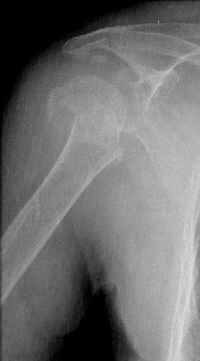

Hello,I am presenting a case of 80 year old male patient right handed known case of hypertension, diabetes and history of CVA 2 years back had a fall in the hosue 10 days back and came to me for pain and ecchymosis around the right shoulder. Xray shows evidence of comminuted fracture proximal humerus extraarticular. He is a doctors father and the doctor wants to know is there any minimally invasive procedure we can do ... I have advised him to go for complete surgery in the form of the AO locking plate under general anesthesia. He is a little reluctant for complete general anaesthesia. My questions to the house is ...1. Is there any other option besides the locking plate ?? (Less invasive) 2. If he is not medically fit for surgery, then can we leave him alone if yes what are the chances of going it into non union? Awaiting your reply Dr Neeraj Bijlani

CT scans would be useful to evaluate the head.

Fragments now look severely displaced.